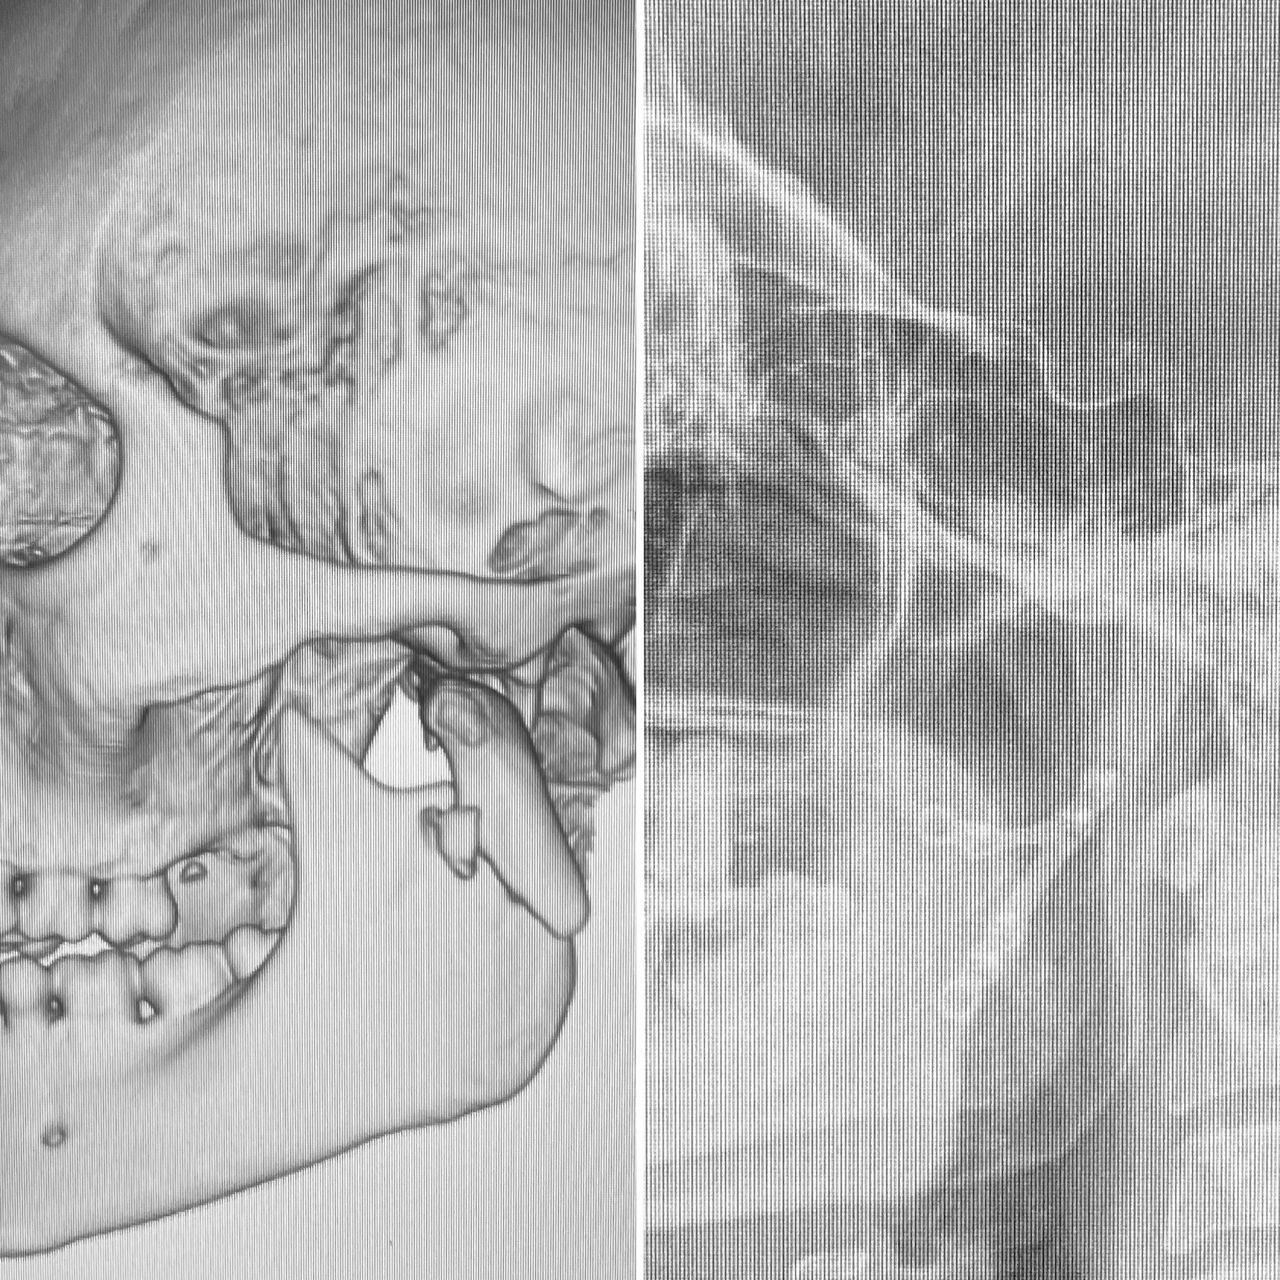

I have experience in oral surgery procedures such as: simple extractions, extraction of impacted teeth and third molars, biopsies, frenectomies, dental implants, zygomatic implants, juxta-osseous implants, and guided bone and tissue regeneration.

In the field of maxillofacial surgery, I have experience in the surgical management of facial trauma, dentofacial anomalies, temporomandibular joint dysfunction, mandibular reconstruction, facial cosmetic surgery, blepharoplasty, otoplasty, mentoplasty, facelifts, lip lifts and lip repositioning, removal of facial biopolymers, and orofacial harmonization.